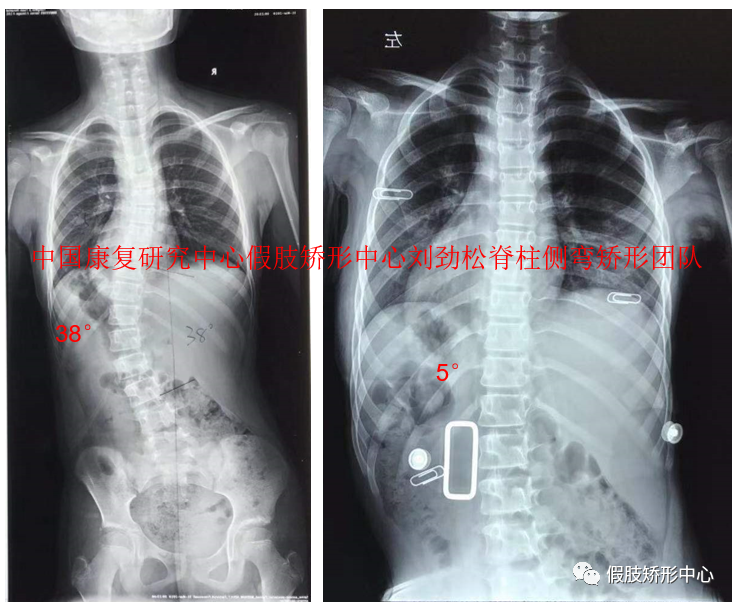

SCS脊柱側彎矯形器個案

2019年假肢矯形中心舉辦索本海姆SCS脊柱側彎矯形器培訓班,得到學員的一致好評。近兩年利用3D數字化技術完成SCS脊柱側彎矯形器近千例,效果良好。